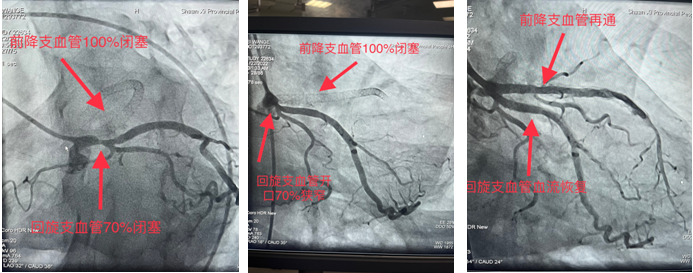

一患者月余前在外院行冠脉手术,手术未成功,遂前来六合彩网站求医,心血管内一科收入,并于11月22日安排冠脉手术为患者诊治病症。造影显示前降支支架内100%闭塞,回旋支开口70%狭窄。由于血管闭塞时间久,且之前支架内完全闭塞,术中出现心律缓慢、血压下降等危险因素。最终,在心血管内一科张勇主任医师、潘硕副主任医师、马彦鹏主治医师及介入放射诊疗手术室护师郭朝望、技师吴华楠等的默契配合和共同努力下,陈旧性冠状动脉闭塞血管得以再通,心脏血流恢复,生命体征随之好转,手术顺利完成。